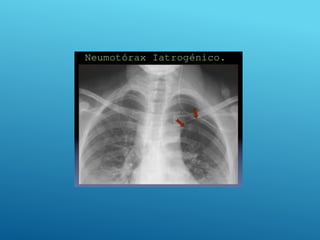

NEUMOTÓRAX

El neumotórax se define

como la acumulación de aire

en el espacio pleural con

colapso secundario del

pulmón

Neumotórax simple